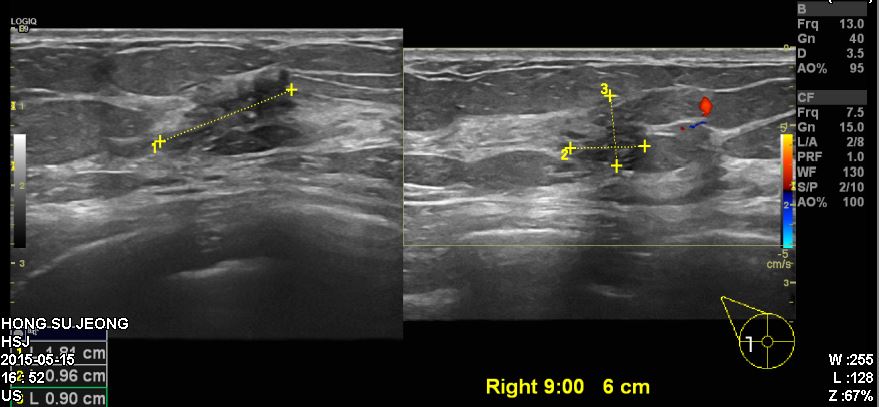

건강검진상 이상 소견으로 내원하신 60대 여성 분으로 우측 9시 방향에서 6cm 떨어진

부의의 혹 조직검사 사행하여 우측 유관암 진단 되었습니다.